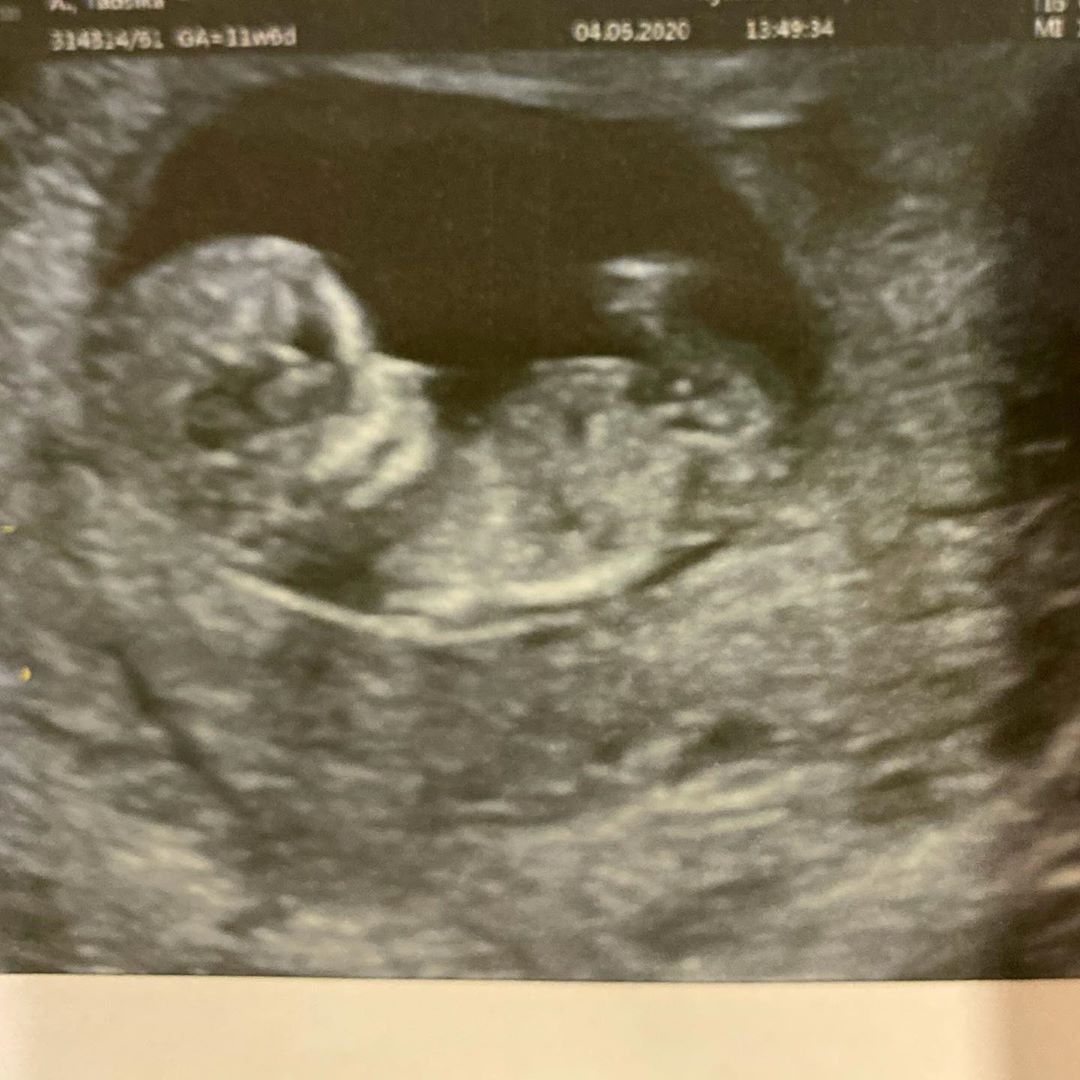

แต่ล่าสุด (4 มิถุนายน 2563) กระต่าย ทรรศิกา เผยภาพอัลตราซาวด์ลงอินสตาแกรม พร้อมบอกข่าวที่อดเป็นห่วงไม่ได้ เนื่องจากคุณหมอบอกว่าเธออยู่ในภาวะ รกเกาะต่ำ ซึ่งเสี่ยงกับการแท้ง จนหมอต้องให้ยากันแท้ง และข้อห้ามอีกมากมายที่ทำให้คนเป็นแม่ทรมานใจไม่น้อย เพราะต้องให้น้องภูผาเลิกกินนมจากเต้า และห้ามอุ้มลูกอีกด้วย

โดยระบุข้อความว่า น้องของภูผา ตัวยังเล็กมาก วันนี้นอนคว่ำโก่งก้นมองไม่ค่อยเห็น วันนี้ไปหาหมอซาวด์มา น้องของภูผาอายุครรภ์ 3 เดือน แต่ที่น่าเป็นห่วงคือ คุณหมอบอก "รกเกาะต่ำ" หมอเลยสั่งห้ามให้เฮียภูผาเลิกเต้า เลิกดูดนมแม่ และห้ามแม่อุ้มลูกโดยเด็ดขาด อันตรายต่อน้องในท้อง !! ด้วยความที่แม่อยากให้ลูกดูดเต้าให้ได้นานที่สุด และแม่อยากเลี้ยงลูก อุ้มลูกเองอย่างใกล้ชิด ไม่คิดว่าจะเกิดเหตุการณ์แบบนี้

วันนี้คุณหมอจ่ายยากันแท้งมาให้ทาน และคืนนี้เป็นคืนแรกที่แม่ต้องให้ภูผาอดนมจากเต้า ขอกำลังใจให้เฮียภูผาหน่อยคับ ภารกิจเลิกเต้าวันที่ 1 แม่นมคัดเต้าตึงเจ็บต้องทำไง ? ใครเคยมีประสบการณ์แนะนำแม่หน่อยค่ะ